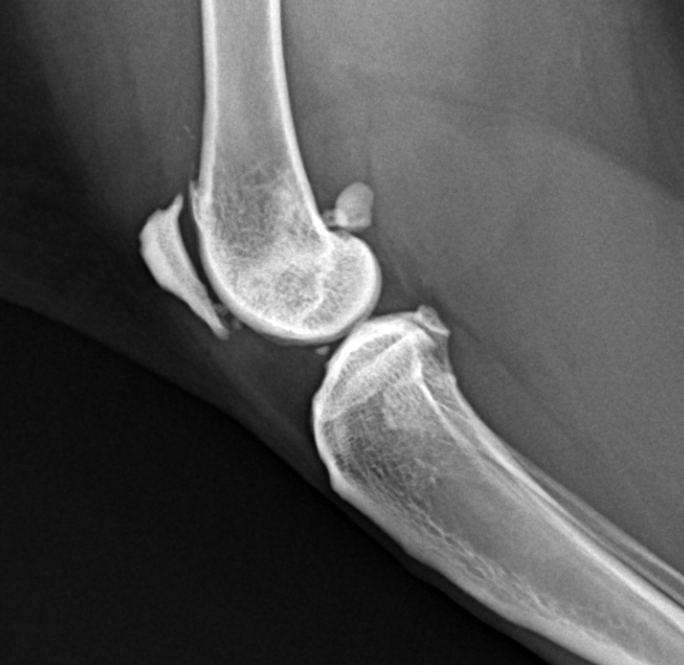

feline joint mice radiography sample